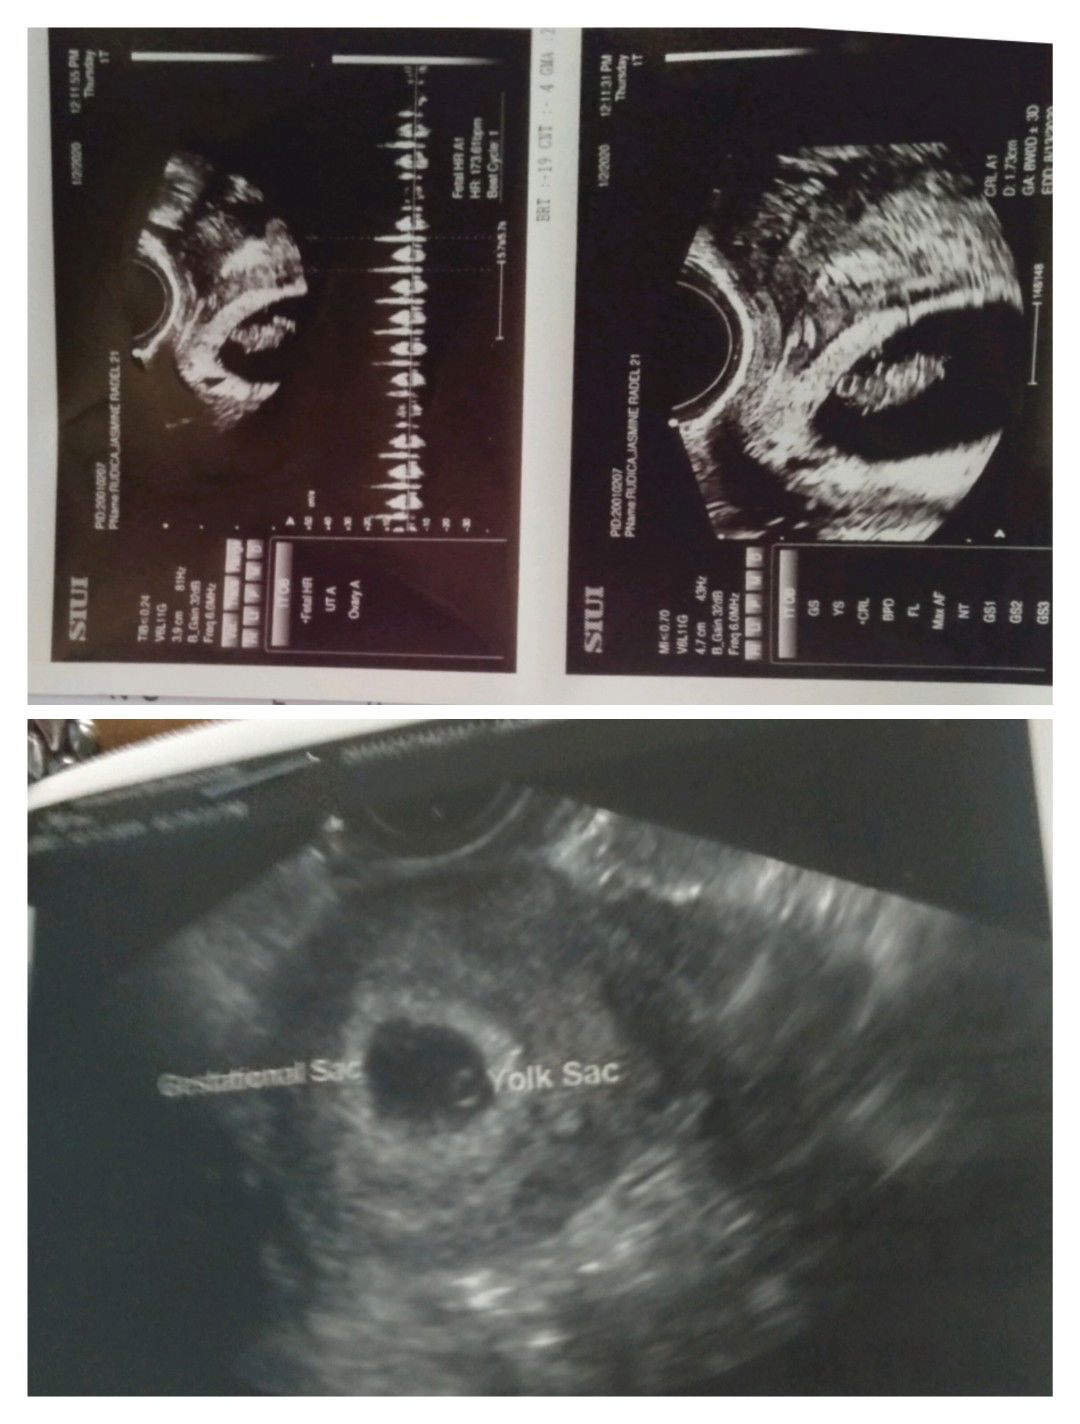

Normal po ba sa 5 weeks and 6 days ng Gestational sac at Yolk sac palang ang makikita??